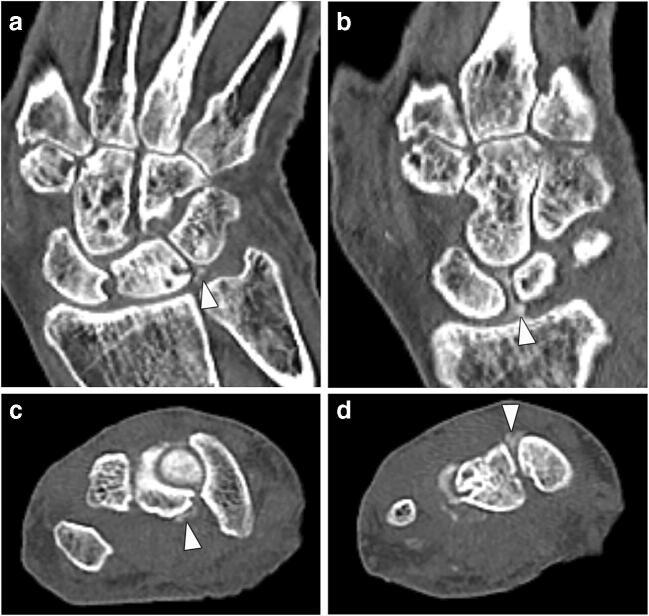

This retrospective study included 28 patients (18 with CPPD, 10 controls) who underwent DECT of the wrist. Collagen density maps were reconstructed from the DECT datasets and used to measure densities in regions of interest (ROIs) placed in the scapholunate (SL) ligament (dorsal, palmar, proximal), lunotriquetral (LT) ligament, and extensor carpi radialis (ECR) tendon, (n = 260 measurements). The presence of calcifications on standard CT images in these regions was assessed by a blinded reader. Densities were compared with nonparametric tests, and linear regression analysis was performed to investigate the impact of age, sex, and CT- detected calcium deposition on collagen density.

本回顾性研究纳入了 28 例患者(18 例 CPPD,10 例对照组),均行腕部 DECT 检查。从 DECT 数据集中重建胶原密度图,并用于测量放置在舟月(SL)韧带(背侧、掌侧、近侧)、月三角(LT)韧带和桡侧腕伸肌(ECR)肌腱的感兴趣区(ROI)中的密度(n=260 个测量值)。由一位盲法读者评估这些区域标准 CT 图像上的钙化情况。使用非参数检验比较密度,进行线性回归分析以研究年龄、性别和 CT 检测到的钙沉积对胶原密度的影响。